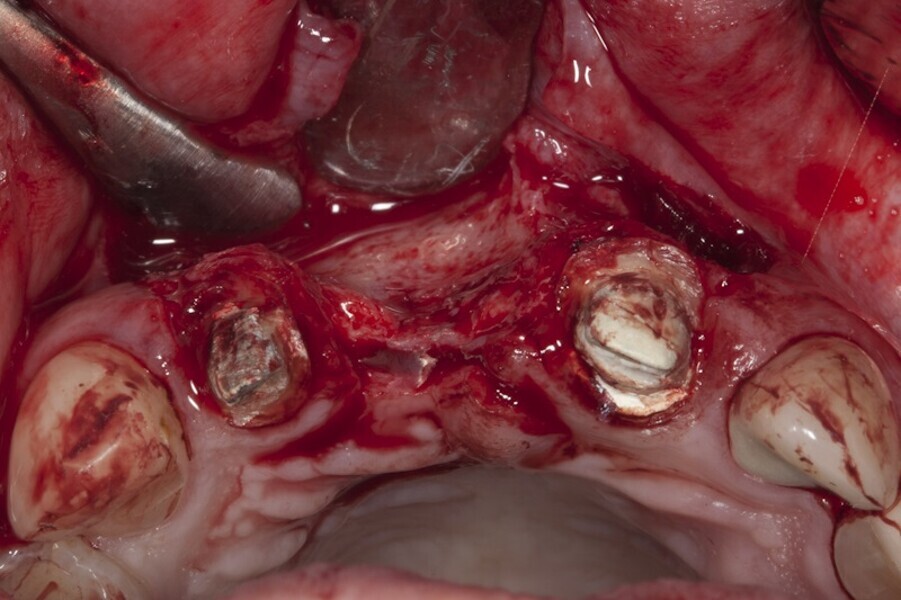

Biomodulacja laserem Nd:YAG z użyciem głowicy Genova®